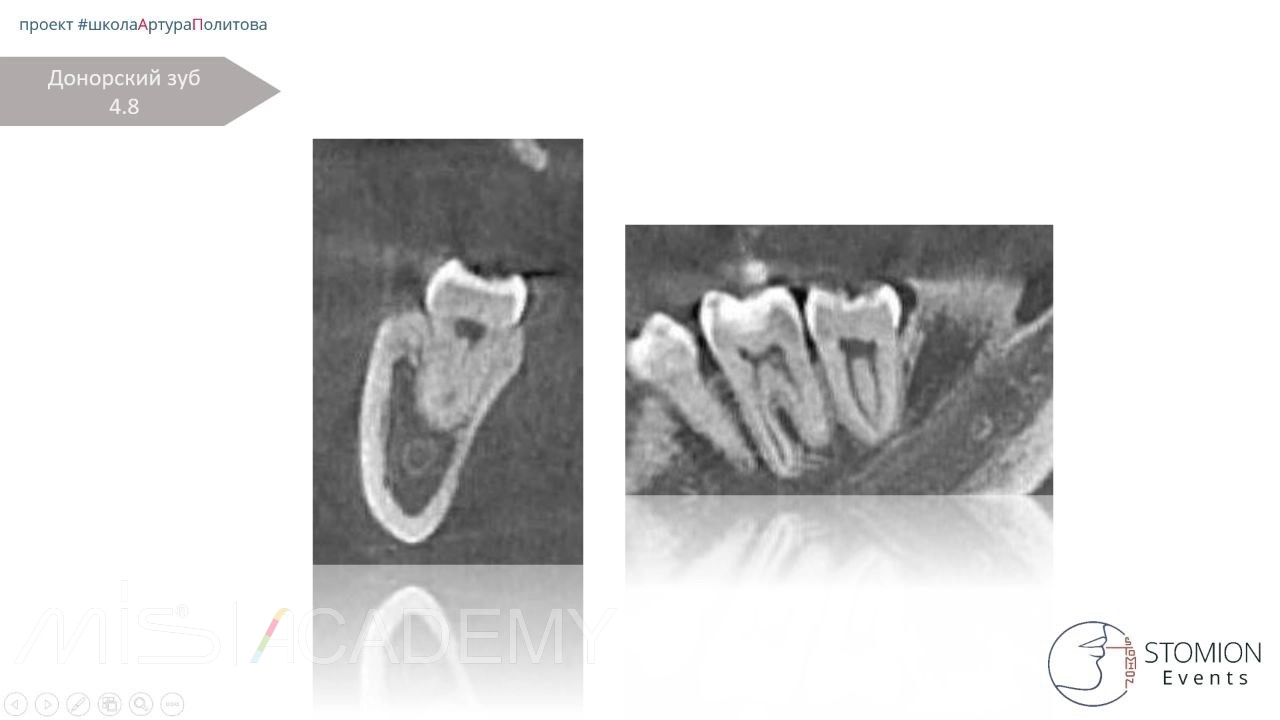

• Одновременно удалён зуб 4.8, трансплантирован в область адентии 1.6 с ТКСЛ.

• Контрольное КЛКТ.

• Через 6 месяцев — контрольное КЛКТ и осмотр.

• Исход положительный, костная регенерация и интеграция трансплантата.